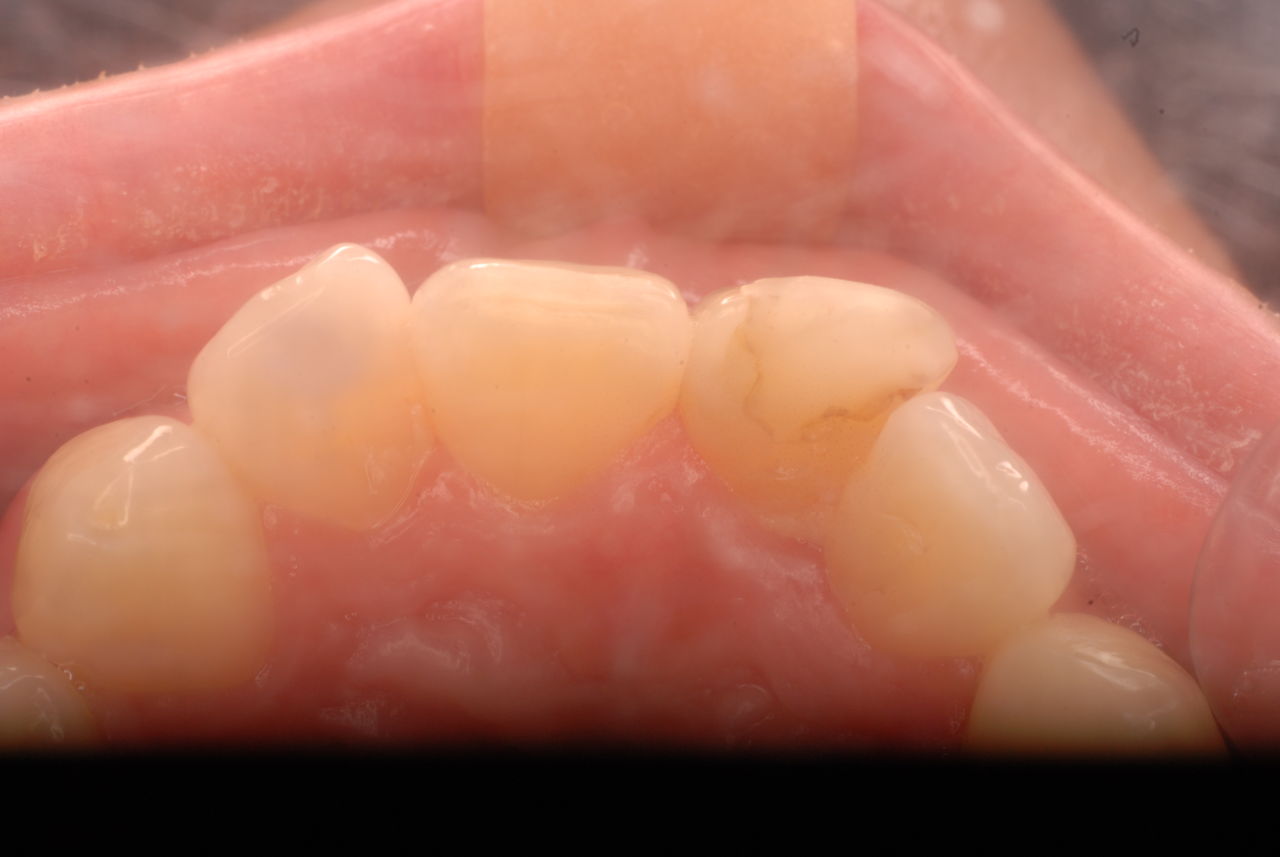

1、先ず一番目は、10才、右の前歯が反対咬合と言って上の歯と下の歯が逆の位置にあり、他の部分があまり咬合していない10才の子供の例でした。噛むと痛みが突然出てしばらく続いていたという症例。

診断を咬合性(歯と歯の噛みあわせ)の急性歯髄炎(神経の炎症)と判断したが、では治療はどうすればいいのかという相談。

レントゲンと話の内容から、食いしばりや歯ぎしりによるものではなく、単純にぶつかる歯が少ないので、その時に前歯のところで何か硬い物などを噛んだために外傷性の痛みが来たのではないかという判断でした。炎症でもないので、奥歯にマウスピースなどを入れて前歯を当たらなくした後に、症状が緩解したら、反対咬合という上下の前歯の関係を簡単な小矯正で変更した方がいいという診断と治療方針の提案で解決しました。